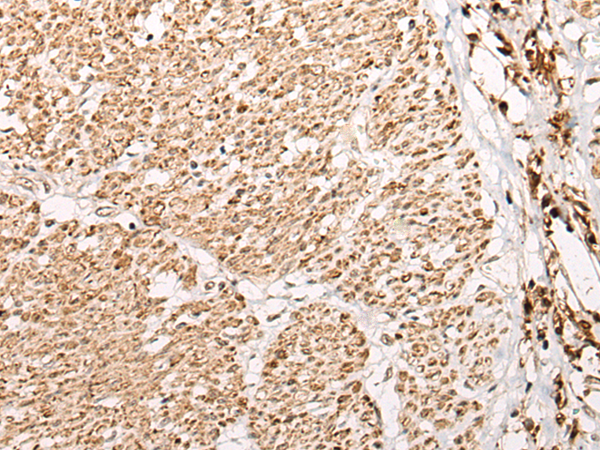

分类: 科研抗体货号: P02307别名: WFS; WFRS; WFSL; CTRCT41应用: IHC反应种属: Human, Mouse